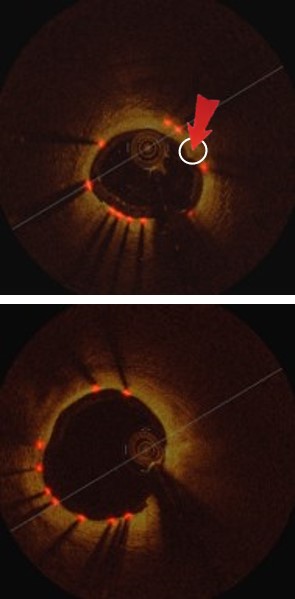

Table 1 shows the detection results of our method compared to the state-of-the-art methods, where it increases recall by 1.2% and precision by 4.7%, relative to the second best results from Faster-RCNN, as shown in Fig 3(a).

Refer to caption

Figure 3: Strut detection results: (a) Comparison of our method to the existing methods, (b) component analysis of our method.

3.3 Component Analysis

Table 1 and Fig. 3(b) show the detection results of our method at individual stages. Fig. 5(a) shows the two example detection results with various thickness coverage. The Local-Network shows the higher recall while Global-Network achieved better precision results (as shown in Fig. 5(c) and Fig. 5(d)). As exemplified in Fig. 5(e), the proposed method integrated both Local Network and Global-Network and achieved a better consistent performance in recall and precision.

Table 1, Fig. 3(b) and Fig. 5 compared the main components of our method individually to quantify their contributions to the final detection results. These results demonstrate that Local-Network has higher recall and we attribute this to the usage of patch-based network to detect all the potential strut candidates. In contrast, Global-Network achieved higher precision for its ability by adding global context, e.g., appearance information, as part of the learning process, which ensures all the detected struts are consistent with the shape of the stent. Table 1, Fig. 3(b) and Fig. 5 also show the advantages from our combination which integrates complementary detection results produced at individual components.